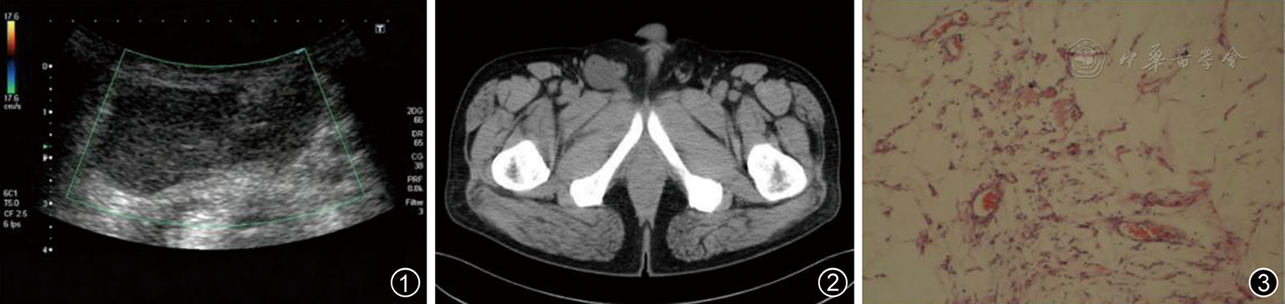

图1~3 腹股沟浅表性血管黏液瘤患者超声、CT及病理图像。图1为超声示不均质低回声团块,形态不规则,后方回声无增强;图2为CT示囊性包块影,增强后未见强化;图3为黏液样基质中见大量梭形细胞,内含多量薄壁狭长的血管